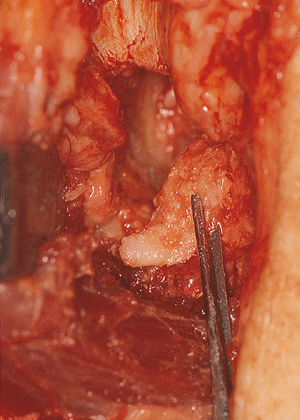

![]() |

|

Figure 20-19.

The debridement consists of a large olecranon osteophyte and of the foramen resection. The coronoid osteophyte was also removed. |